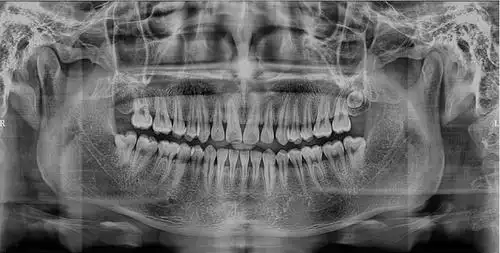

牙医520重磅发布这台有ai的口腔cbct来了